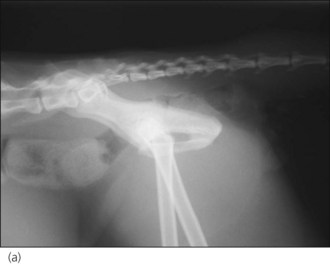

Pneumothorax

image image

Figure 28.2 (a) Right lateral and (b) dorsoventral thoracic radiographs of a cat showing pneumothorax and pulmonary contusions following trauma.

image

Figure 28.3 Right lateral thoracic radiograph of a dog showing traumatic tension pneumothorax. The dog underwent cardiopulmonary arrest just prior to arrival at the hospital and the owner did not want resuscitation to be attempted.